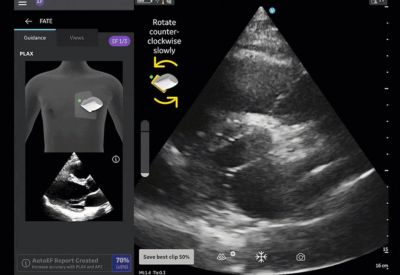

T-Mode Heart works by applying advanced AI models to live ultrasound images in real time. As the clinician scans the patient’s heart, the system automatically recognizes and labels essential anatomical structures including the left ventricle, right ventricle, atria, valves, pericardium, and major vessels while providing visual guidance on probe positioning and image optimization. The tool also displays standard cardiac measurements (ejection fraction estimation, chamber dimensions, and pericardial effusion assessment) and offers educational overlays explaining normal versus abnormal findings, helping users build competence rapidly.

The solution is fully integrated into Clarius’s wireless handheld ultrasound scanners, requiring no additional hardware or complex setup. It supports multiple cardiac windows (parasternal long-axis, short-axis, apical four-chamber, and subcostal views) and is designed to work in both emergency and routine primary care settings. Early feedback from pilot users indicates that T-Mode Heart significantly reduces the time required to acquire diagnostic-quality cardiac images and improves diagnostic confidence among non-specialist physicians.